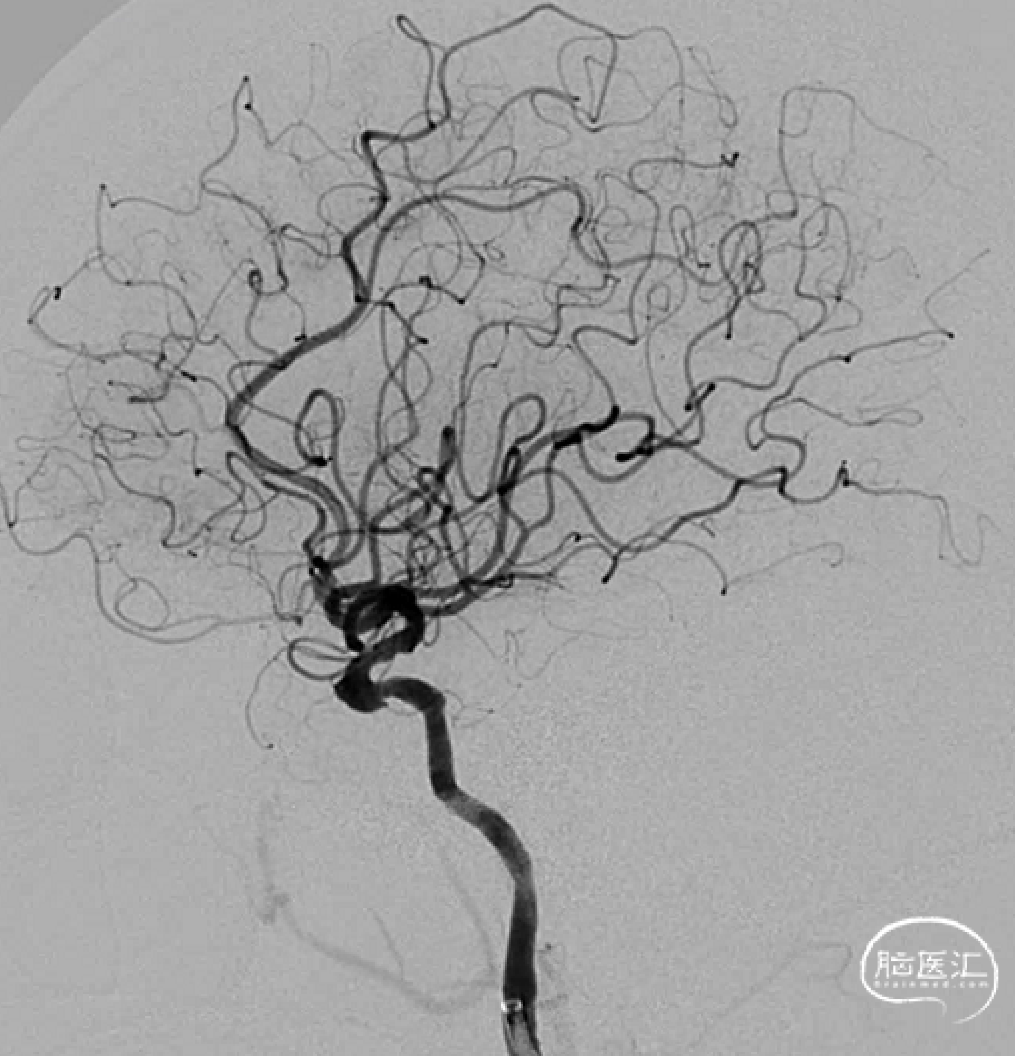

术前影像

脑血管造影(主动脉弓造影及后循环)

右侧颈动脉造影

左侧颈动脉造影

左侧颈内动脉重建(左侧狭窄及扩张较右侧更甚)

手术过程

经Cat5完全释放支架后,拉推送杆后支架近端打开,后将Cat5跟进血流导向装置内尝试“按摩”,支架整体贴壁不够理想。

Cat5通过后海绵窦段狭窄即较前改善

Cat5提供稳定通路,引入3.5mm×10mmHiryu球囊扩张由远端及近端扩张狭窄段及支架贴壁欠佳处

造影示狭窄及贴壁较前进一步改善

导丝成袢,继续“按摩”改善贴壁

“按摩”后再次造影,C2段狭窄仍较明显且贴壁欠佳

再次引入球囊扩张近端

扩张后再次复查造影示支架打开及贴壁较前明显改善

标准正侧位造影未见远端血管栓塞

稀释造影提示支架贴壁可,狭窄改善